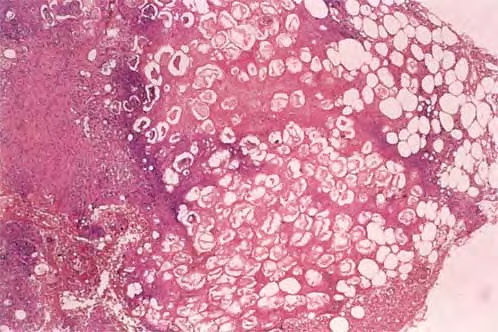

Histopathologically, pancreatic panniculitis is a mostly lobular panniculitis with intense necrosis of the adipocytes at the center of the fat lobule The characteristic features consist of coagulative necrosis of the adipocytes, which leads to ghost adipocytes. Ghost adipocytes are necrotic adipocytes that have lost their nuclei and

show a finely granular and basophilic material within their cytoplasm due to calcification . Often, ghost adipocytes appear grouped in small clusters at the center of the fat lobule, whereas an inflammatory infiltrate of neutrophils is present at the periphery and extends into the adjacent septa. Ghost adipocytes result from the hydrolytic action of pancreatic enzymes on fat, followed by calcium deposition, a process known as saponification. In late-stage lesions of pancreatic panniculitis, fat necrosis and calcified ghost adipocytes are less evident, and the fat lobule is replaced by a granulomatous inflammatory infiltrate composed of foamy histiocytes and multinucleated giant cells. Ghost adipocytes are characteristic of pancreatic panniculitis, but sometimes they are sparse and are only found after serial sections.